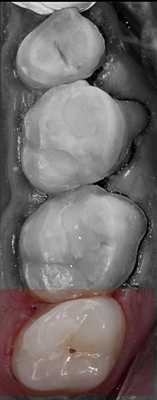

На рисунке 1 показана исходная ситуация.Классический фиссурный кариес зубов 16 и 17. Как и в большинстве подобных случаев, кариозный процесс протекает абсолютно бессимптомно.

После изоляции рабочего поля (рис. 2) и механической отчистки от налета с поверхности зубов снимается ключ bite-силиконом с учетом габаритов клампа (рис. 3) .

Внешний вид окклюзионного ключа показан на рисунке 4 .

После этого, если есть желание, можно воспроизвести характеристики с помощью композитных красок. Вид после финишной отделки и полировки (рис. 10) .

Окклюзионная коррекция, как правило, минимальна или вообще отсутствует. Вид реставраций через двое суток (рис. 11) .